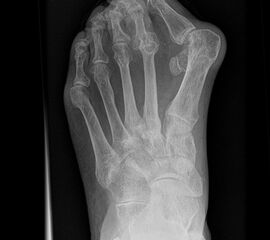

Fuß dp (dorsoplantar) mit Belastung

Kennzeichen des Röntgenbildes:

• Standardabbildung des Fußes zusammen mit der belasteten seitlichen Aufnahme und der unbelasteten Schrägaufnahme.

• Die belasteten Aufnahmen liefern relevante Informationen zur Fußstatik und sind die Grundlage aller achskorrigierenden Eingriffe an Vor- und Rückfuß.

• Sämtliche Winkelbestimmungen beziehen sich auf belastete Aufnahmen.

Besondere Bemerkungen zum Beispielbild:

• Schwere Hallux valgus Deformität.

• Die Sesambeine sind luxiert, ebenso das Großzehengrundgelenk. Luxation des Metatarsophalangealgelenks II.

• Degenerative Veränderungen der tarsometatarsalen (TMT) Gelenkreihe, betont TMT II und III.